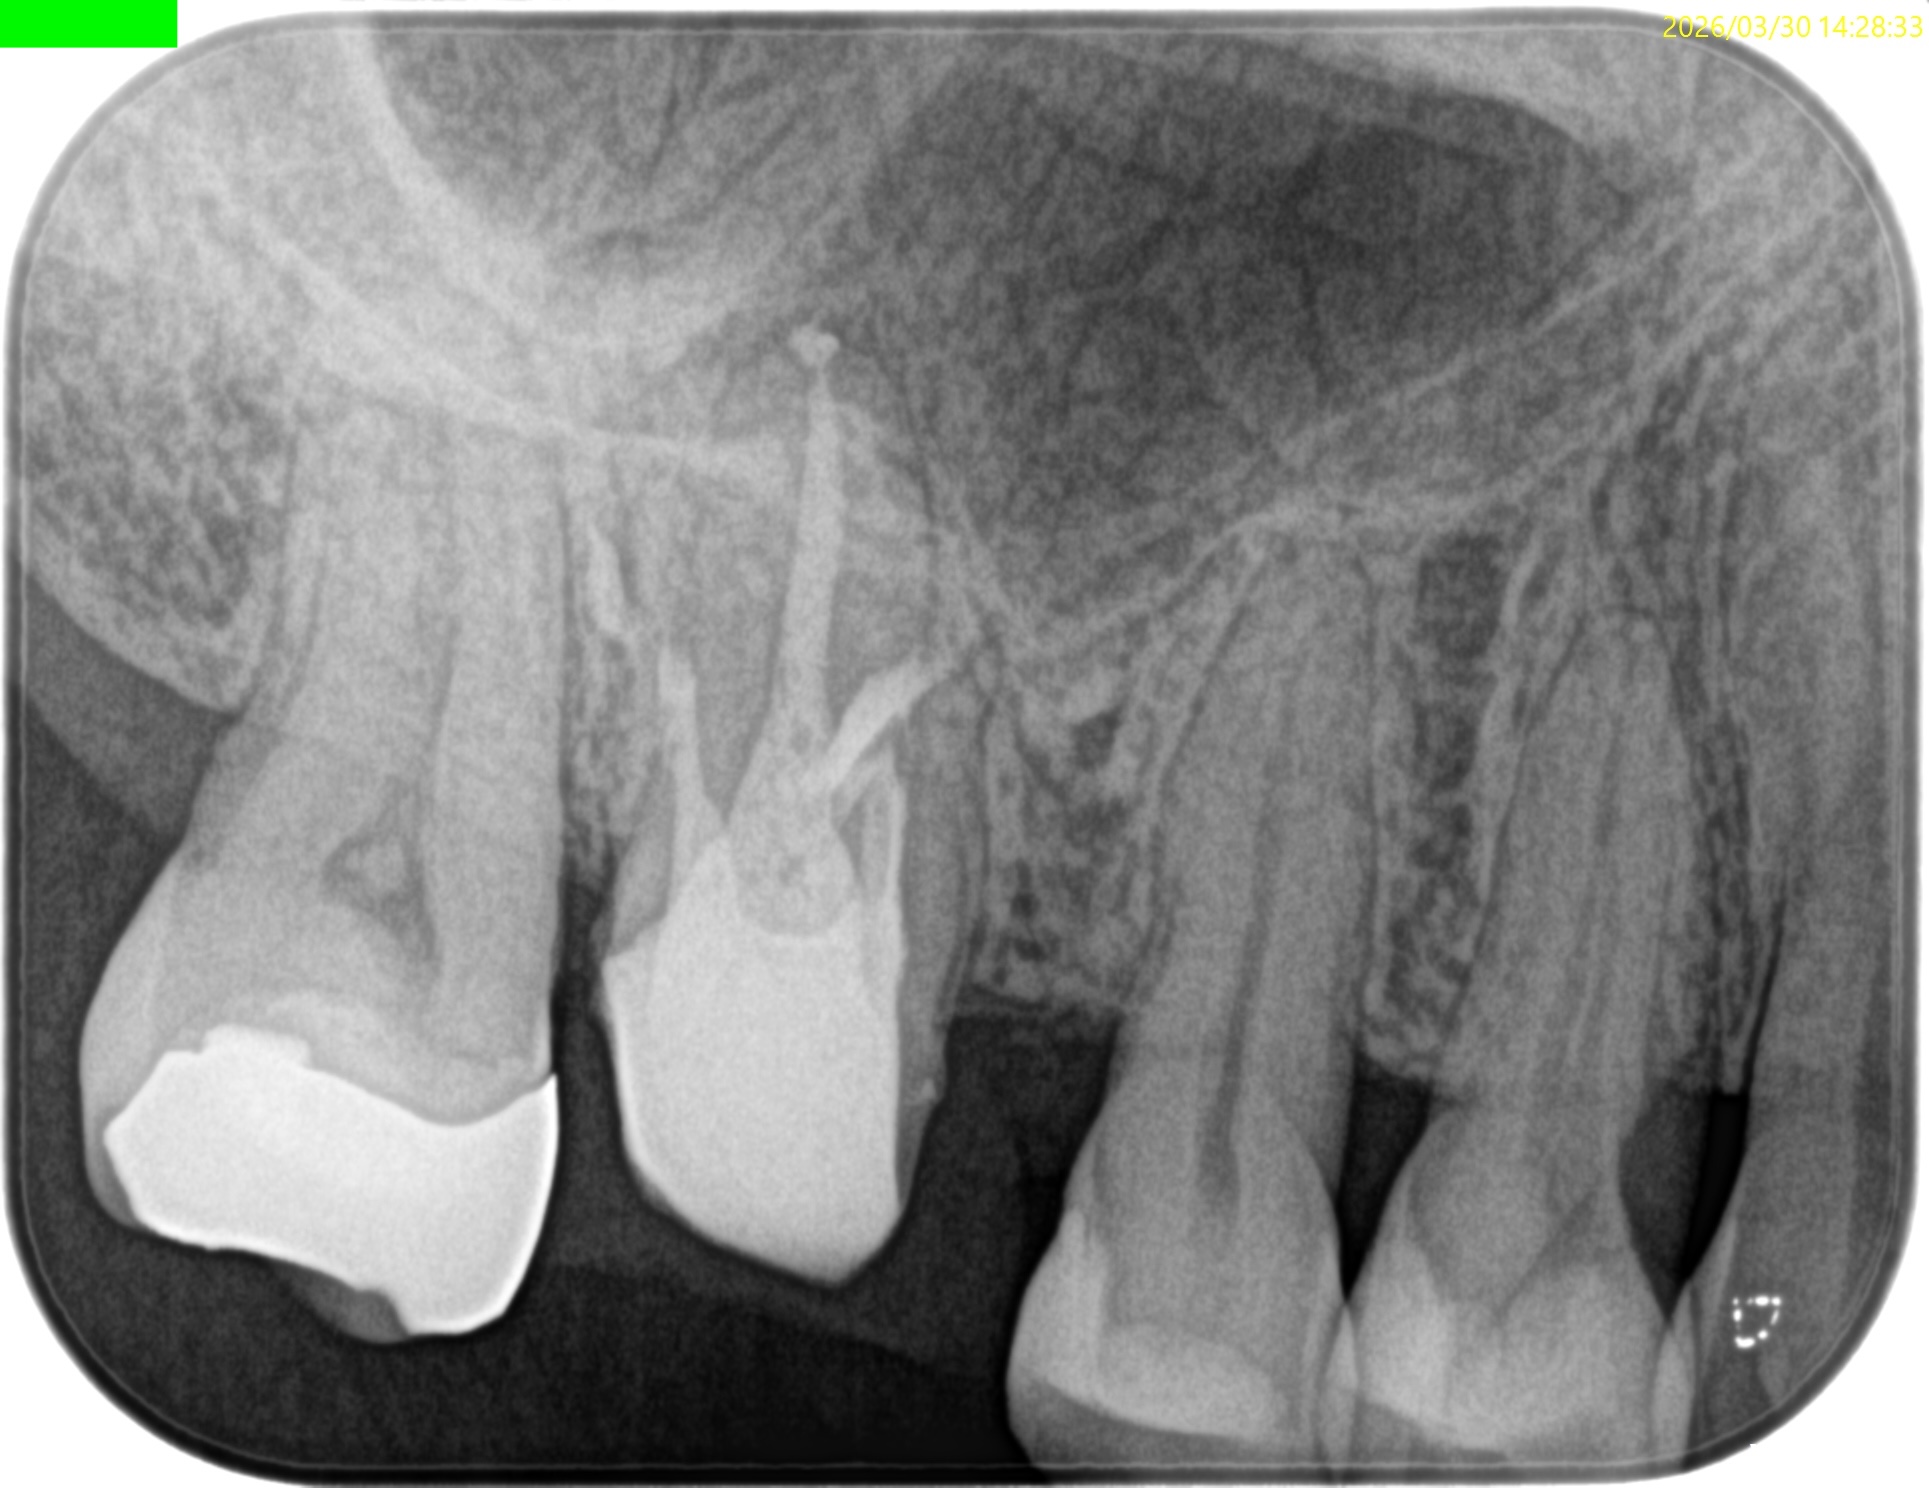

#3 MB, DB Apicoectomy 7M recall(2026.3.30)

MB

DB

P

B

7ヶ月前と比較した。

劇的に歯槽骨の開創は回復している。

そしてP根だが、根尖病変の治癒とともに口蓋側の骨欠損が大きく回復しているのがわかる。

Primary Endo Secondary Perioに見えた

のに、だ。

(歯周ポケットが正常なので歯周病ではないので上記表現は正しい表現とはいえない)

これは単純にエンドだけの問題であったのだ。

そして、

エンドの治療のみでここまで回復していることがこの歯内療法の治療のパワーを示している。

患者さんはSRPなどの歯周治療は一切していない。

HyFlex EDM #60.02でわずか数mm形成しただけなのに、ここまで歯槽骨が回復している。

ともかく、これで最終補綴もOKだ。